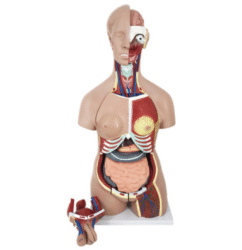

ATL-11 MALE MUSCLES FIGURE INTERNAL ORGANS HARD

The model is an anatomically accurate representation of the human anatomy, complete with superficial and deep musculature, the digestive system, lymphatic system, respiratory system, urinary system, circulatory system, endocrine system, and nervous system. Our model has removable organs and dissectible features for a complete educational experience.

Classification:

Skeleton Models(human bone, muscle, etc.)